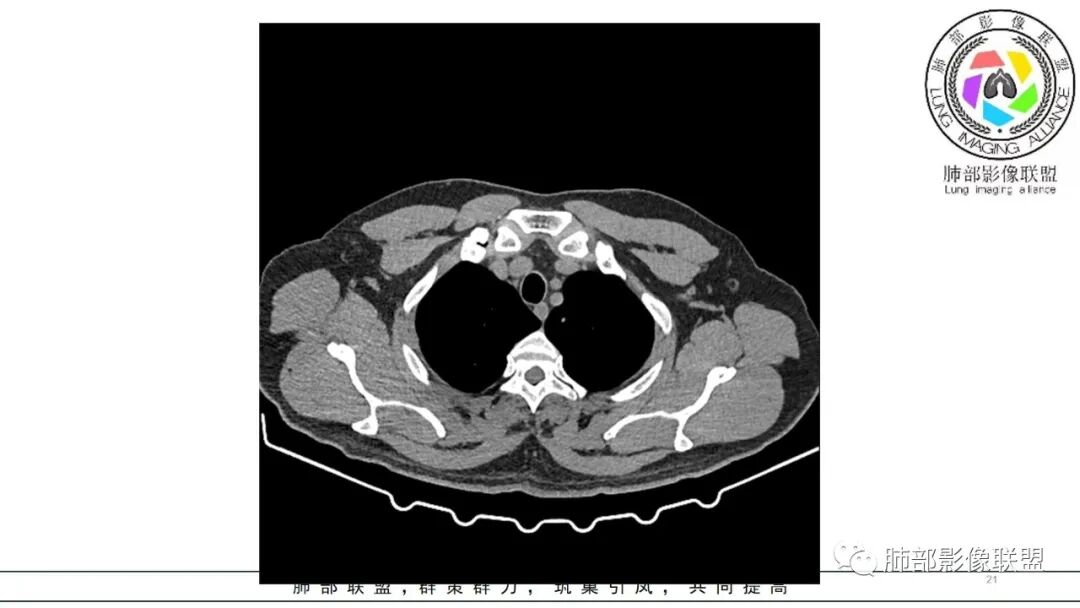

中年男性,咳嗽咳痰低热三天。右肺中叶、下叶条片状高密度影,局部边缘有晕,可见卫星灶。双肺另见多发小结节。考虑炎性肉芽肿,PC,鉴别GPA

中年男性,咳嗽咳痰伴发热3天,有鼻窦炎、 中耳炎病史,血沉、 CRP 增高,中性粒稍高。

双肺多发实性小结节,边清,多位于胸膜下。右肺中叶不规则实变影,沿支气管血管束走行,似有跨叶。

中年男性,咳嗽咳痰发热,鼻炎中耳炎,血沉高,右肺中叶条状高密度实变影,边界清楚 ,双肺散在小结节,部分小空洞,首先考虑GPA,鉴别结核

男,47岁,咳嗽咳痰发热三天,既往中耳炎病史。CT示双肺多发随机分布小结节,多位于胸膜下,部分伴小空洞,右肺中页不规则实变影,沿支气管血管束走行。实验室检查血沉,CRP增高。综合考虑为感染性病变,隐球可能,鉴别GPA

中年男性,咳嗽咳痰、发热三天。

CRP及血沉高。

既往中耳炎病史。

双肺多发结节,以胸膜下分布为主,形态相似,边缘较规整,少部分边缘晕征,无分叶毛刺;右肺中下叶多结节融合并实变影,边缘平直、U形征,跨叶。